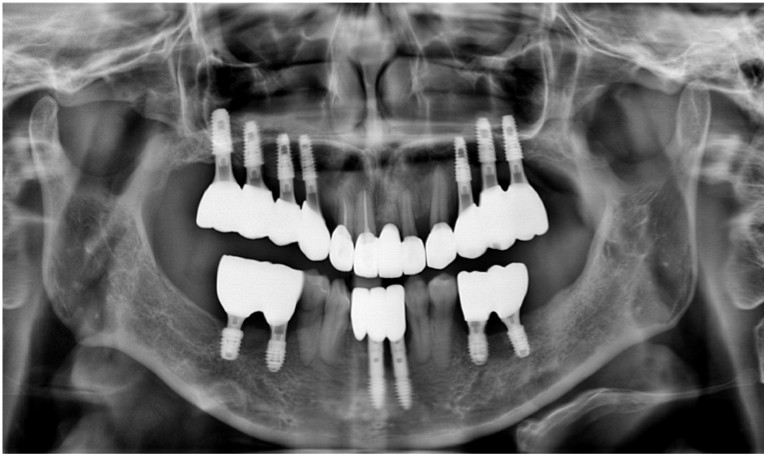

환자분께서는 2년 반쯤에

내원해 주셨던 적이 있으셨는데요.

위 사진은

그 당시 파노라마 사진으로

그때도 만성 치주염 진단을 받으셨지만

지속적인 치료와

관리가 잘되지 않아

현재 더 심해진 상태입니다.